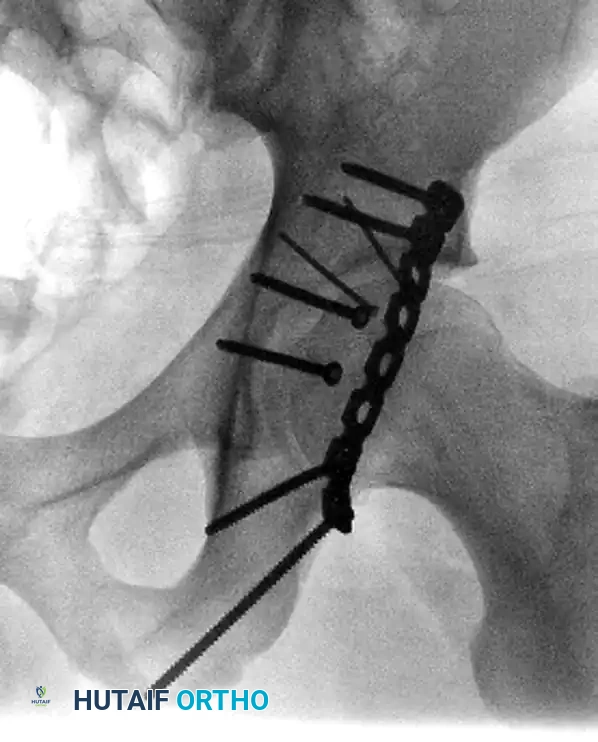

Considerations in the Elderly Patient

Historically, ORIF was performed in the elderly to preserve bone stock for future reconstructive surgery. Today, this paradigm has shifted. In elderly patients with severe comminution, osteopenia, or pre-existing osteoarthritis, achieving anatomical reduction is often impossible.

In these cases, two modern strategies are employed:

1. Percutaneous Fixation: Limited column fixation using percutaneous fluoroscopic techniques to prevent gross displacement, allowing the fracture to heal in a stable position prior to a delayed Total Hip Arthroplasty (THA).

2. Acute Total Hip Arthroplasty: Primary THA combined with limited internal fixation (to stabilize the acetabular shell) is increasingly advocated for elderly patients with poor prognostic fracture patterns, allowing immediate full weight-bearing.